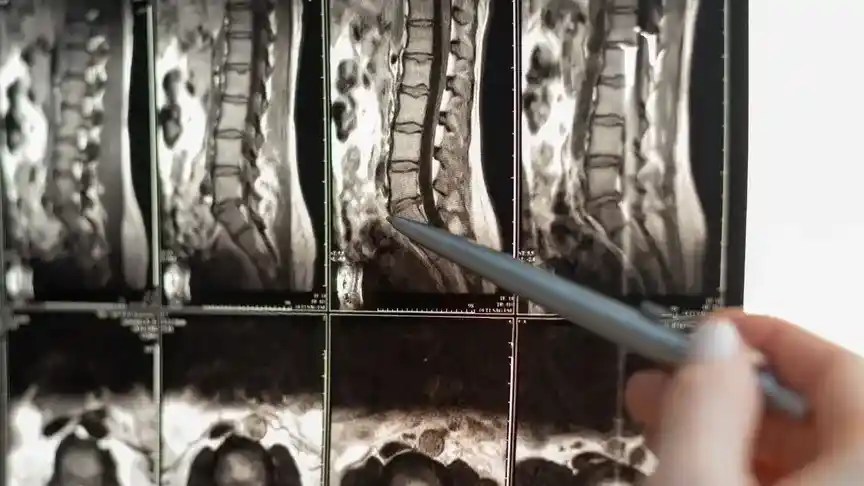

Przyczyną dyskopatii kręgosłupa jest nadmierna kompresja krążka międzykręgowego. Nie jest to oczywiście osiowa kompresja, ponieważ powstałe wypukliny są najczęściej usytuowane z jednej strony kręgosłupa. Dla przykładu – wypuklina powstała z prawej strony kręgosłupa może dawać poniżej wymienione objawy do prawej nogi.

Dyskopatia – mechanizm powstania

Aby to zobrazować dla przykładu załóżmy, że mięśnie znajdujące się z lewego boku naszego ciała są zbyt napięte, to powoduje przechylenie tułowia do bocznie, nieprawidłowe ustawienie miednicy no i oczywiście mocne uciśnięcie krążków międzykręgowych z lewej strony.